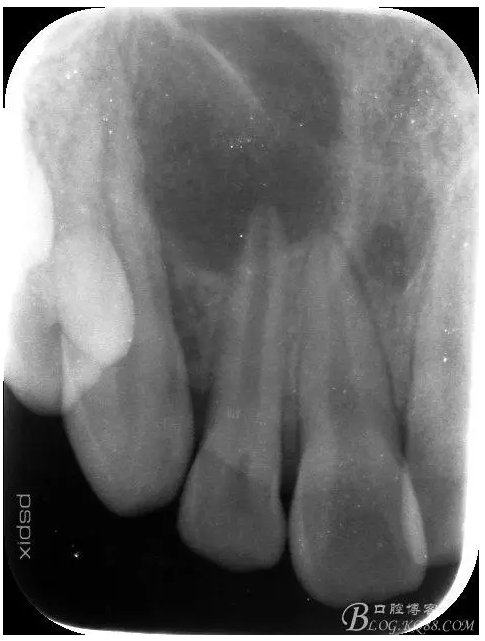

患者、宋xx,男、16歲。主訴:右側(cè)面部腫脹三天。并自覺鼻腔溢膿。專科檢查:患者右側(cè)眶下區(qū)腫脹隆起,皮膚未變紅,觸痛不明顯,鼻腔檢查未見瘺口。也無(wú)滲出物流出。口內(nèi)檢查:12牙冠未變色。舌側(cè)有一畸形溝,唇側(cè)前庭溝粘膜紅腫隆起,未見 有瘺道觸診有乒乓感,x線檢查:12根尖孔未徹底發(fā)育完成,根尖有橢圓形陰影,大小如花生米,邊界清楚。診斷:12根尖囊腫。處理建議:建議 1.抗感染治療,控制感染的根尖囊腫。2.感染消退后行12根管治療+手術(shù)摘除囊腫+根管倒充填。患者同意治療方案,簽手術(shù)知情同意書。

1.術(shù)前的根尖片檢查及根管治療影像: